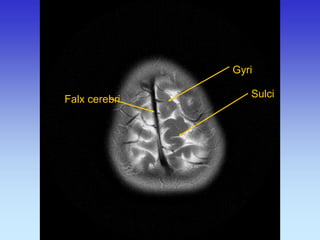

Gyri

Sulci

Falx cerebri

Calvarium

Superior Sagittal Sinus

Straight Sinus

Transverse Sinus